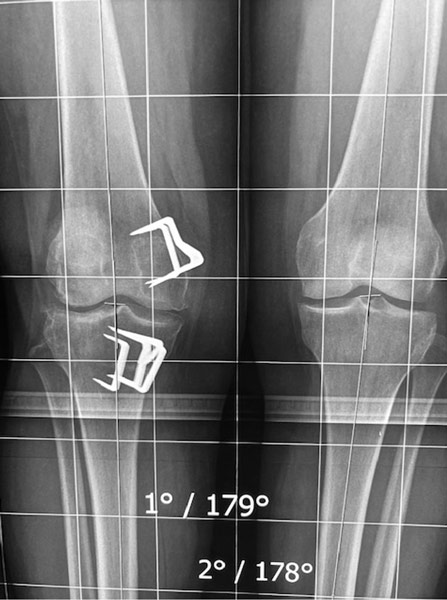

Sur ces radios de face, il n’y a pas de pincement donc pas d’arthrose au genou droit; il y a un pincement entre le fémur et le tibia au genou gauche.